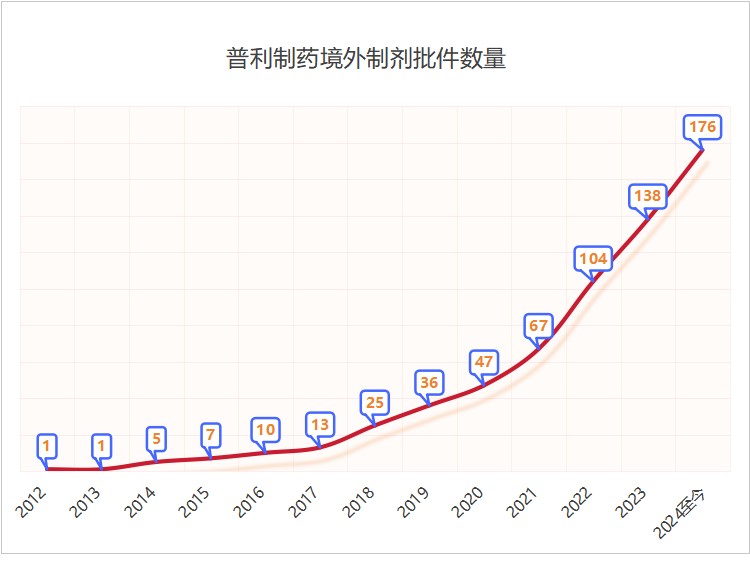

国际批文爆发增长

经过不断地学习与积累、创新与发展,普利制药全球化事业迎来了收获期,药品国际化批文爆发式增长。截至目前,普利制药已取得欧美等市场的制剂生产批件176个,其中美国批件36个。2023年,普利制药获得美国批件9个,全国排名第二;2024年年初至今,普利制药已获得美国批件13个,全国排名并列第一;普利制药国际化批文审评中78个,待递交的国际化品种近200个,众多产品正在加速获批中。